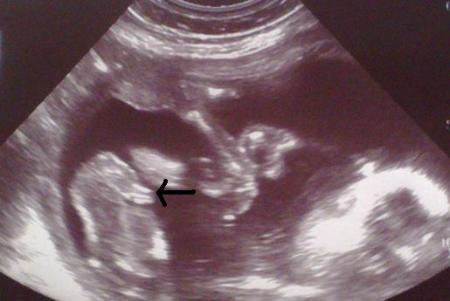

Ich bin eine April 2011 Mama und hab mal schnell ein Bild von meinem Buben rausgesucht

Bild zu

bub :-) Aus der 15.SSW